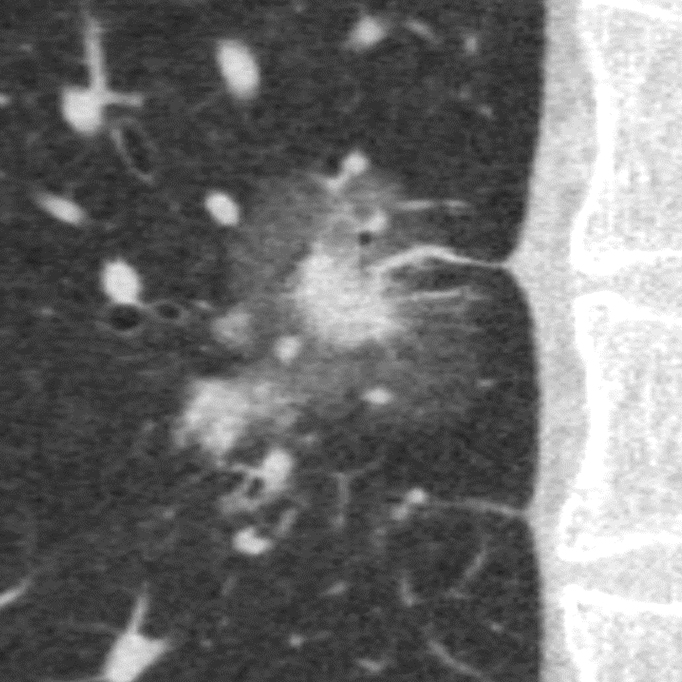

Клінічні приклади

Порівняння звичайної роздільної здатності з ультрависокою роздільною здатністю (УРЗ)²

КТ з ультрависокою роздільною здатністю 0,25 мм ³